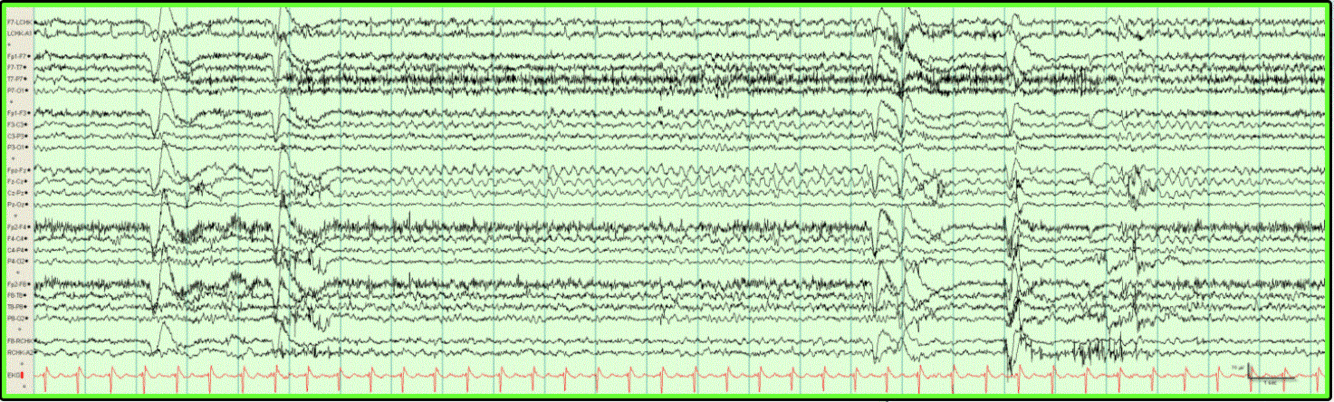

RMTTD (Psychomotor variant)

• Theta

• Midtemporal

• Unilateral/bilateral

• Does not evolve or spread to other sites

• 5-15 seconds duration

• Wake (less during drowsiness and disappears during light NREM sleep) (? Research this)

• Teen/adult